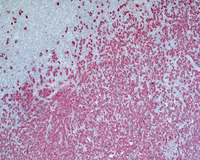

Figure 6: Areas with variant patterns

Patterns D and E are notable for nodules that are rich in T-cells. This is seen as negative cells within the nodules on CD20 stain noted below. Images show pattern D in the images below. Note that residual small B-cells are present in the background of these nodules.

Although not depicted, Pattern C is notable for LP cells located in the immediate vicinity of the nodular structures extending into the internodular areas.